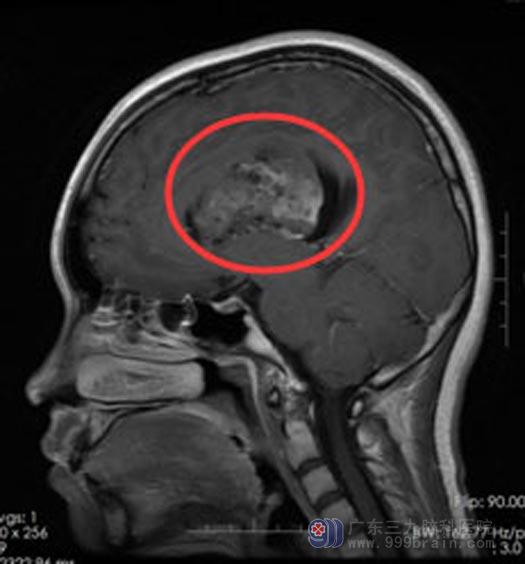

术前核磁共振,显示脑室内肿瘤巨大

广东三九脑科医院进一步脑MR+波谱+弥散检查提示:左侧侧脑室室间孔区巨大占位性病变,考虑为中枢神经细胞瘤可能,并左侧侧脑室梗阻性脑积水。肿瘤巨大占位效应明显,直接手术风险极大,中枢神经细胞瘤对放疗敏感,为减少手术风险,经多学科讨论后,决定先放疗再手术。

一周的放疗结束后,鲁明主任主刀在全麻下行“左侧侧脑室巨大肿瘤切除+脑室外引流+硬脑膜修补术”,取左侧经额中回入路,术中见肿瘤呈灰白色,质软,血供丰富,显微镜下将肿瘤分块全部切除。术后病理提示:不典型中枢神经细胞瘤,WHO II级。